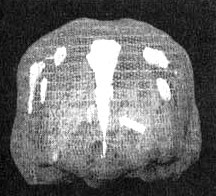

Трехмерное изображение — активный мозг

Иллюстрация к книге — Измените свой мозг - изменится и жизнь! [i_057.jpg]

Трехмерное изображение — активный мозг, вид сверху